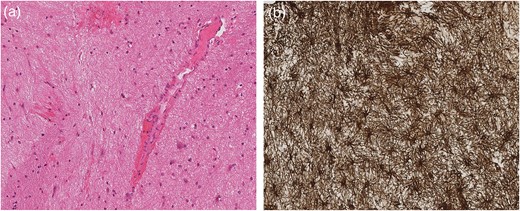

A third MRI performed in late September 2014 during an acute admission for worsening visual symptoms demonstrated interval enlargement of the midbrain mass (Fig. 2a and b) featuring acute petechial haemorrhage (Fig. 2c). There was no restricted diffusion or contrast enhancement at any time point. Sagging of the brainstem was evident on both studies in 2014, unchanged from the initial scan performed 2 years earlier.

Comparative axial T2 images demonstrating growth of the midbrain mass between early (a) and late (b) September 2014. The coronal T1 image from September 2014 (c) reveals petechial haemorrhage (arrow) in the lesion with corresponding susceptibility artefact on gradient echo imaging (not shown).